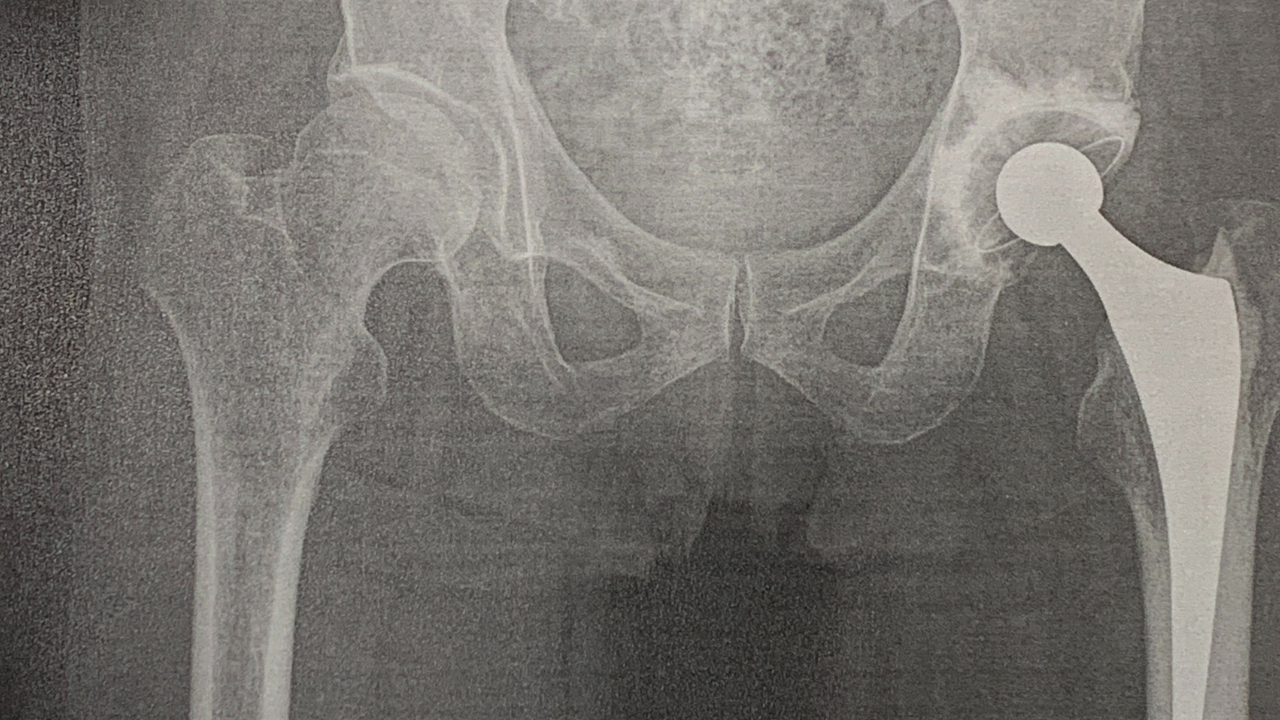

骨粗しょう症なの?

グレーゾーンである事は確かで

認めたくなくても 身体は正直で

『左股関節頭下骨折』で入院、

「人工関節置換術」なる手術を受けて

8週間(60日間)の入院生活を・・。

股関節 レントゲン画像.png

18万円近い支払いを余儀なくされ

将来(老後)の見通しが立ちません。

不安な日々を送っています。